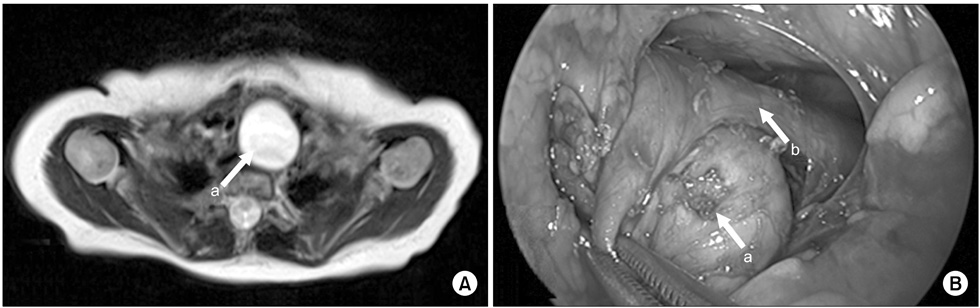

Fig. 4

Esophageal duplication cyst of superior mediastinum. (A) There was a mass situated at just front of upper esophagus on neck MRI (2.5×2.2×4.5-cm-sized mass). (B) There was a mass at the front and right of the esophagus. Arrows: a, esophageal duplication cyst; b, true esophagus.

Fig. 4 Esophageal duplication cyst of superior mediastinum. (A) There was a mass situated at just front of upper esophagus on neck MRI (2.5×2.2×4.5-cm-sized mass). (B) There was a mass at the front and right of the esophagus. Arrows: a, esophageal duplication cyst; b, true esophagus.